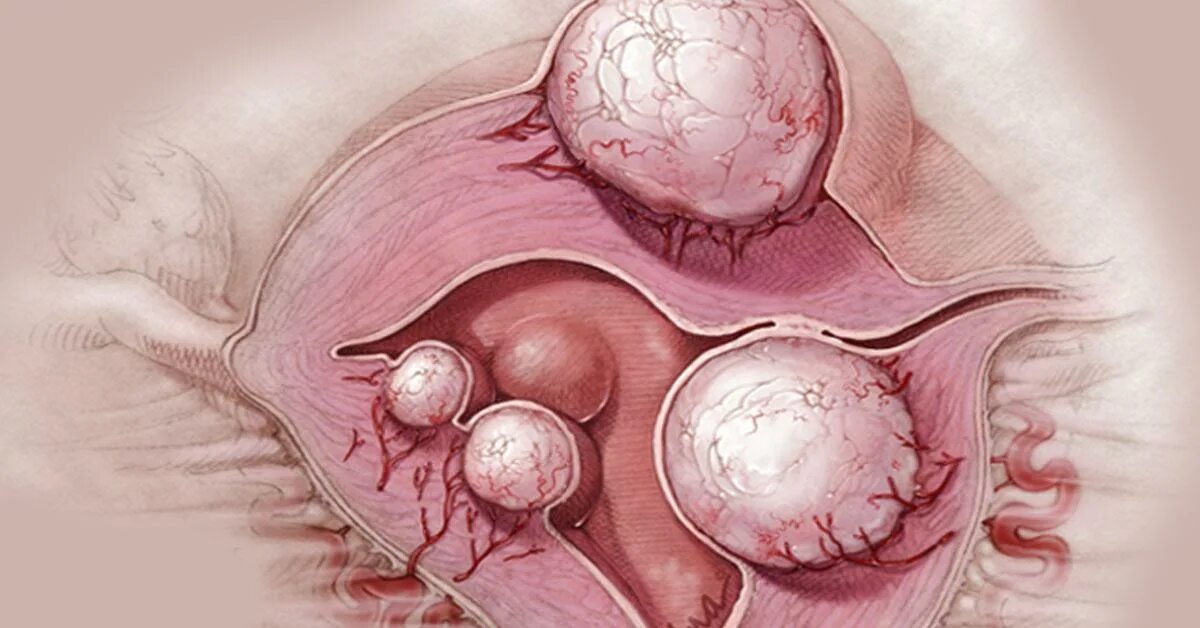

Интрамуральный узел тип 4